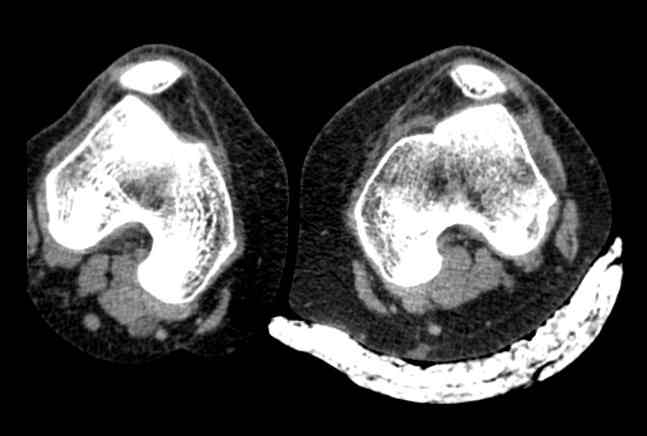

привычный вывих надколенника + patella alta

Обратилась молодая женщина с повторным вывихом надколенника, повторный вывих в октябре 2013. после чего находилась в гипсе и ортезе. Сейчас сгибание - 90. Снимки прилагаю. Планирую латеральный релиз и medial plication. Достаточно ли этого будет? Другие варианты?